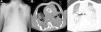

Rapid clinical deterioration ensued, with severe respiratory failure refractory to optimal medical therapy and non-invasive ventilation (blood gases: pH 7.14; pCO2 74 mmHg; pO2 32 mmHg; SO2 41%; and lactates 5.4 mmol/l). Since it was impossible to intubate and ventilate the patient, even after several attempts at orotracheal intubation guided by bronchofiberscopy, emergency percutaneous tracheotomy was performed. Antibiotic therapy was changed to vancomycin and imipenem, and inotropic support was begun due to hypotension refractory to fluid administration. The chest X-ray revealed diffuse infiltrate and thoracic computed tomography showed foci of bilateral parenchymal consolidation, ground-glass opacification and bilateral pleural effusion (Figure 4).

Chest X-ray showing bilateral parenchymal infiltrate and nodular lesions in soft tissues associated with lipodystrophy (A); thoracic computed tomography at the level of the aortic prosthesis, mediastinal window (B) and lung window (C), showing foci of bilateral parenchymal consolidation, ground-glass opacification and bilateral pleural effusion.